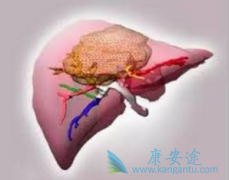

����ԭ���Ըΰ���PLC��Ϊ�������������ʵĵ�5λ�������ҹ��߷���ռȫ��ΰ����ߵ�һ�룬Ҳ�������ʽ��˷ΰ��Ķ������������ڴ�����ΰ��������ڸι��������ټ���֢״�����ԣ�������ϳ����ĺ��٣���������ʱ���Ѵ�ʧ���������ᣬ��˶��������ڵĸΰ����� ...

������ʿ���ϼ��Ž�������������PD-L1����TECENTRIQ��atezolizumab�����ϰ�ά͡�� �����鵥�� ���Ʒ������������FDA����ͻ�����Ʒ��϶���һ���������ڸΰ���ת���Ը�ϸ�������ߡ�HCC �������ԭ���Ըΰ����͡�����ͻ�����Ʒ��϶����ǻ��� TECENTRIQ �� ...